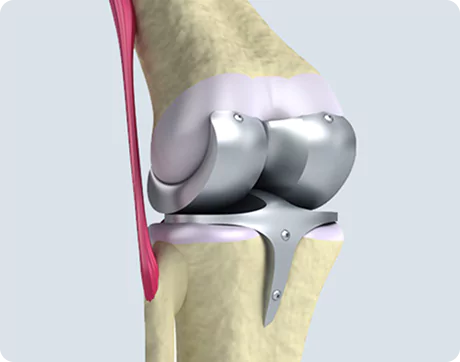

What Is Spine Surgery?

Spine surgery is a medical intervention aimed at treating conditions that affect the spinal column and spinal nerves. It becomes necessary when conservative treatments such as physiotherapy, medications, or injections fail to relieve persistent symptoms like chronic back pain, sciatica, or nerve compression.

The spine is a complex structure composed of vertebrae, discs, nerves, and ligaments. Problems in any of these areas can lead to severe pain, restricted movement, or neurological symptoms. Spine surgery helps to correct structural abnormalities, relieve pressure on spinal nerves, stabilise the spine, and restore function.